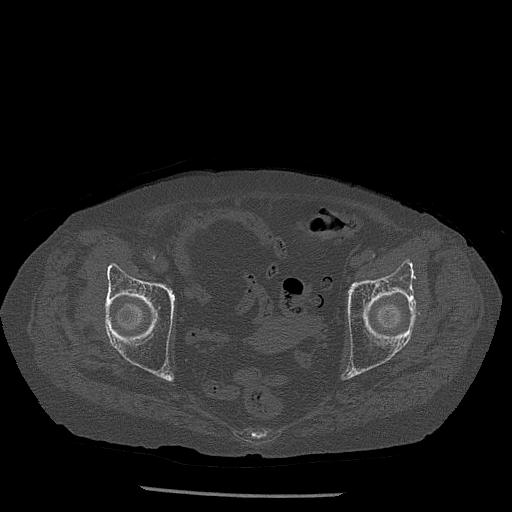

100703 1/27 両股正面+軸 1/29 両股正面+軸 94歳女性 パンソンロン